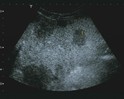

L'ambulatorio privato si svolge prevalentemente il pomeriggio presso gli studi di Via Tarantelli, 1 di Avezzano. La visita gastroenterologica viene sempre accompagnata da una ecografia addominale. L'ecografia addominale, che prevede anche uno studio delle anse del tenue, delle pareti gastriche e del colon, rappresenta un elemento fondamentale per stabilire un iter diagnostico o terapeutico. L'ecografia intestinale anticipa molto di quello che una semplice endoscopia può rilevare. Si pensi alla diagnosi di appendicite o a quella di una diverticolite, dove l'ecografia rappresenta lo strumento più affidabile per la diagnosi e la stadiazione. Ancor più importante è ruolo svolto dall'ecografia nella stadiazione delle malattie infiammatorie intestinali come malattia di Crohn o colite ulcerosa. Nel Crohn, in particolare, l'ispessimento transmurale e l'eventuale interessamento di altre anse intestinali, sono aspetti colti dall'esame ecografico in maniera dettagliata, a volte anche superiore all'esame RMN o TAC.

L'ecografia in termini specialistici viene definita ultrsonografia. Gli esami ecografici consentono di visualizzare e valutare lo stato degli organi interni attraverso l'utilizzo di ultrasuoni.